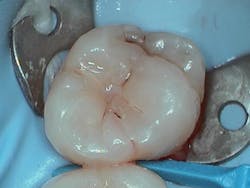

Restoring the proximal wall initially allows more time for the dentin bond to mature before adding subsequent dentin replacement layers, thus lessening polymerization stress. Preoperative radiographs of the affected tooth were taken, confirming deep initial decay on tooth no. 15 (figure 1). An ideal restorative environment and isolation were achieved with a rubber dam. A light blue Isodam (Four D) was utilized, which provides better visual clarity and light reflection. The Isodam was anchored with a W8A clamp (Hu-Friedy) for better restorative access when placing sectional matrices after cavity preparationNext, a sectional matrix (Garrison Dental) was placed and burnished with a spoon to facilitate a broad adaptation of the band to the adjacent tooth (figure 4). A Palodent V3 ring (Dentsply Sirona) was placed for separation and to ensure a tight resultant contact.

Clearfil Majesty ES-2 Universal composite (Kuraray Noritake) was selected as the restorative material. It provides easy adaptation due to its creamy consistency that prevents adherence to instruments. This composite material maintains its shape and contours prior to curing, allowing the clinician to create anatomy during placement. As this composite is a universal shade, it allows theSelective-etch technique was employed on the exposed and uncut enamel, followed by an application of Clearfil SE Protect Primer and Clearfil SE Bond. The bonding agent was lightly thinned with air and cured. The composite was placed along the dentin and proximal box margins to achieve a seal around the matrix band.